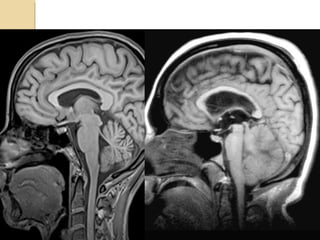

DIFFUSE AXONAL INJURYDIFFUSEAXONAL INJURY Rarely detected on CT ( 20% of DAI lesions are hemorrhagic) MRI:T1,T2,T2 GRE, SWI

DAIDAI Due to acceleration/decelerationto whtie matter + hypoxia Patients have severe LOC at impact Grade 1: axonal damage in WM only -67% Grade 2:WM + corpus callosum (posterior > anterior) – 21% Grade 3:WM + CC + brainstem

DAIDAI Hours: ◦ hemorrhages andtissue tears ◦ Axonal swellings ◦ Axonal bulbs Days/weeks: clusters of microglia and macrophages, astrocytosis Months/years:Wallerian degeneration

BRAINSTEM INJURYBRAINSTEM INJURY Bydirect or indirect forces Most commonly associated with DAI Involves the dorsolateral midbrain and upper pons and is usually hemorrhagic Duret hemorrhage is an example of indirect damage: tearing of the pontine perforators leading to hemorrhage in the setting transtentorial herniation <20% of brainstem lesions are seen on CT